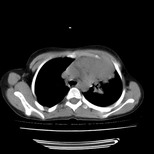

经过胸部穿刺活检为支原体感染。以下示抗支原体感染30天后所见,病灶明显缩小,临床症状消失: